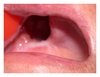

A 46-year-old female patient, from the rural area of the state of Mato Grosso, Brazil, was examined in an oral cancer prevention campaign and presented a lesion in the right side of the hard palate (Figure 1). She reported pain in the region with three years of evolution.